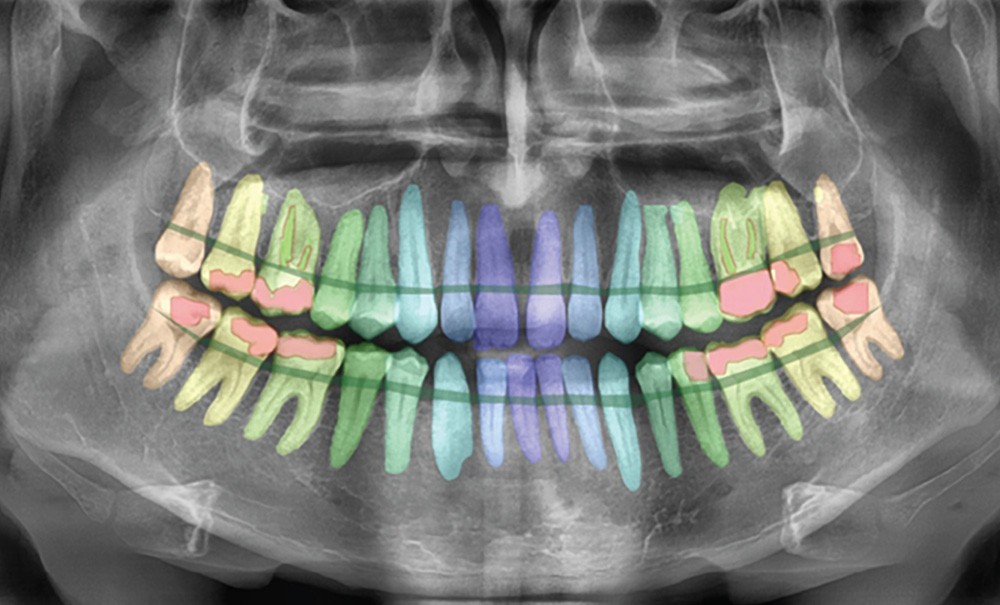

Si l’IA envahit discrètement notre quotidien et que nous, êtres humains, lui faisons de plus en plus confiance, dans la pratique dentaire, nous semblons exprimer plus souvent une certaine méfiance à son égard [1]. Cette méfiance est tout à fait compréhensible, car nos tâches diagnostiques et nos traitements quotidiens exigent un haut degré de précision. En tant que cliniciens, nous ne voulons pas compromettre la qualité des soins prodigués en utilisant l’IA. Cependant, cette dernière peut également être développée sur la base d’un apprentissage supervisé de haut niveau, grâce à une interaction quasi continue et parfaite entre des ingénieurs en IA hautement qualifiés et des dentistes spécialisés. Cette interaction et ces retours d’information sont indispensables pour fournir des renseignements pertinents, non seulement pour le développement de l’IA, mais également pour toute formation complémentaire, validation et résultat clinique [1]. L’IA peut ainsi devenir l’assistant parfait, capable de travailler beaucoup plus rapidement et de manière plus cohérente que le praticien, sans sacrifier la précision [2, 3] (fig. 1). Cependant, l’IA doit être surveillée tout au long de son cycle de vie et apprendre de ses erreurs en étant continuellement soumise à la supervision d’un expert humain à toutes les phases de développement, de validation et de maintenance, avec un retour d’information sur les résultats incorrects renvoyé directement à l’outil d’IA basé sur le cloud. Ce n’est qu’ainsi que l’IA dentaire pourra devenir l’assistant du futur.